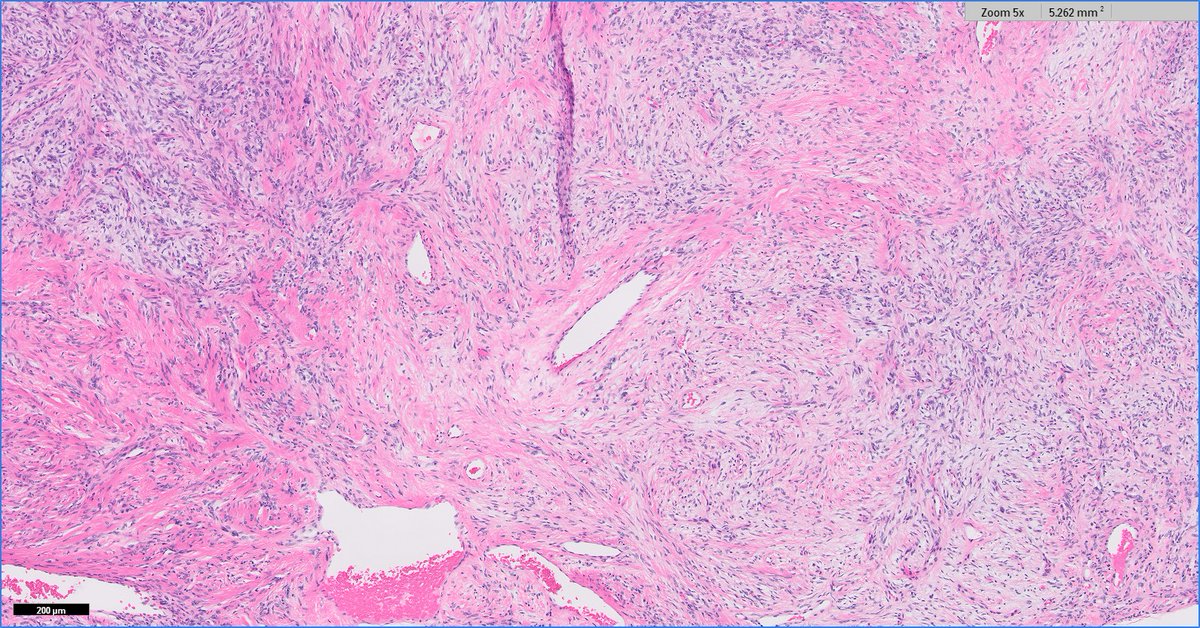

Anatomical Pathologist - UBC #BSTpath #GYNpath